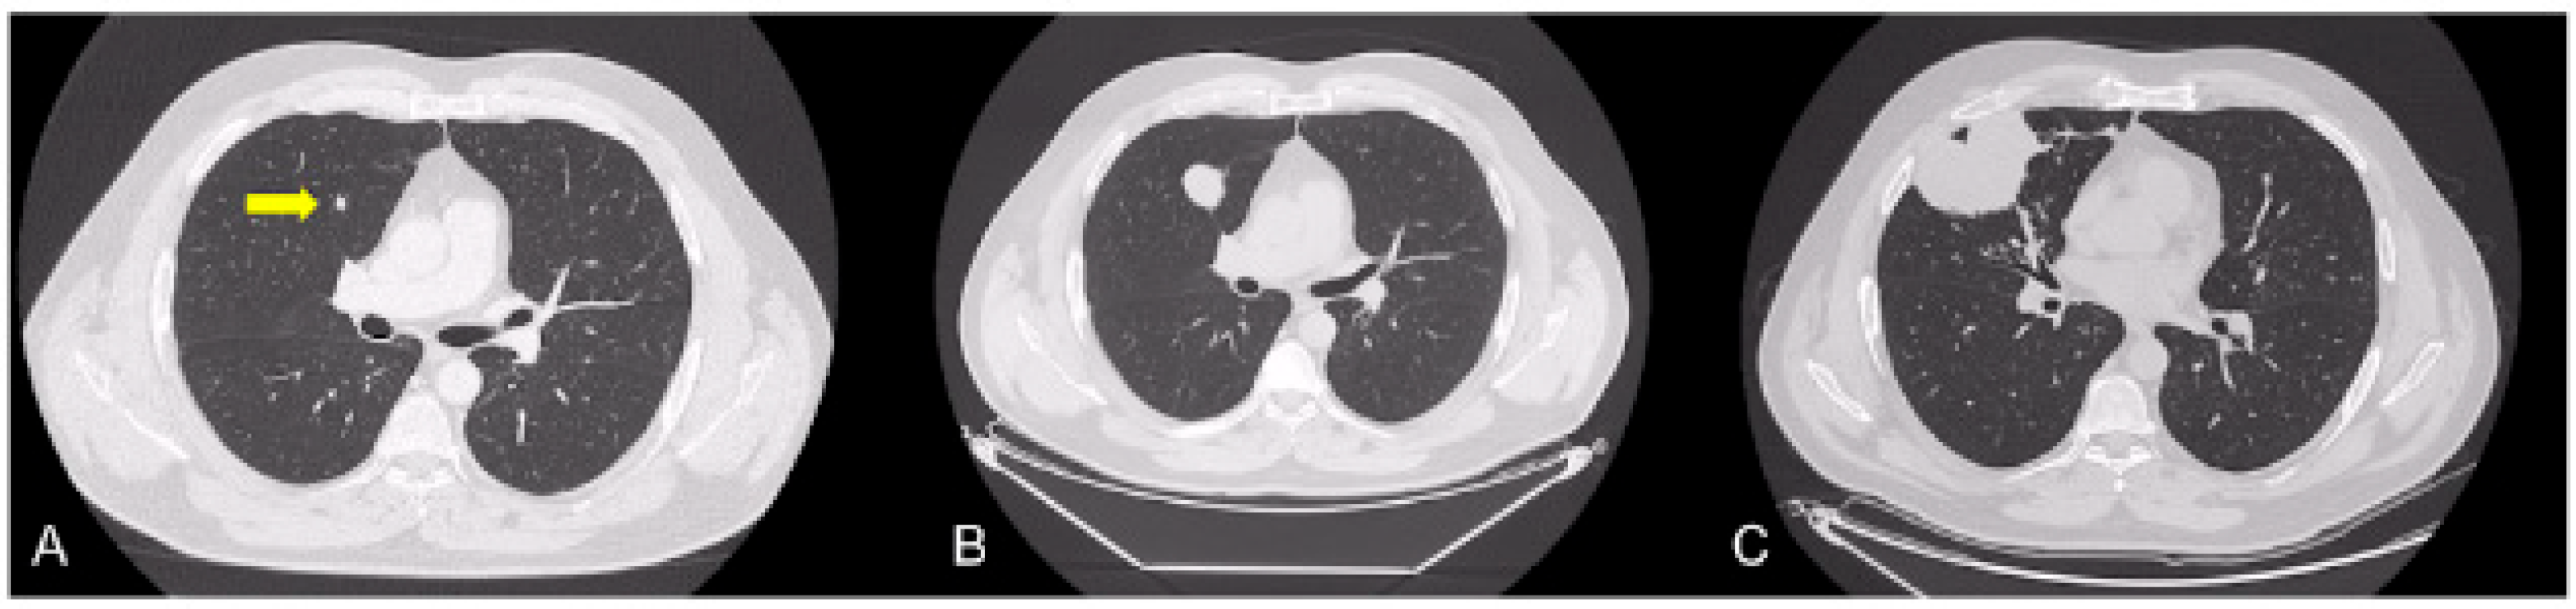

3.1. Case 1